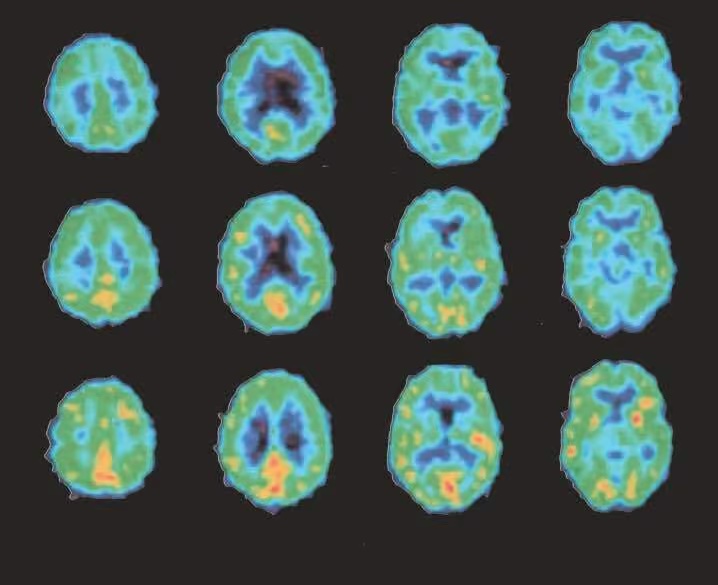

Der erste Monat ist bei allen kritisch – im Hirnscan siehst Du, warum.

Zeile 1: Erster Tag ohne Alkohol

Zeile 2: Nach 15 Tagen kehrt langsam Aktivität zurück

Zeile 3: Nach 30 Tagen wieder weitgehend normale Hirnaktivität.

Die Bilder machen klar, warum die ersten 30 Tage des Ausstiegs so schwer sind. Das Gemeine: Ein Glas Alkohol würde im dämmernden Gehirn sofort wieder ein wahres Feuerwerk entfachen, weil der Alkohol scheinbar wie auf Knopfdruck die Hirn-Aktivität zurückbringt.